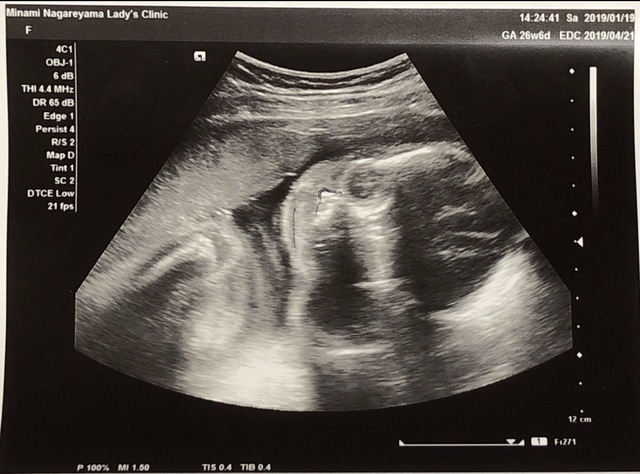

26週0日(26w0d・女の子)|あやんだ さん(25歳)

エコー写真撮影時のエピソード:

これが初めて顔が正面から撮れたときのエコーでした。

それまでは横顔だったり、手で見えなかったりしていたので、やっとハッキリ顔がわかる写真が撮れて、成長してるなー!っていうのが実感出来た時でした。

この写真が「コアラ」みたいだなーと思って、この日からコアラちゃんって呼んでました。 顔が見えると主人も愛着が湧いてきたようで 「早く子どものもの揃えないとね!!」と張り切り出したのもこの頃でした。